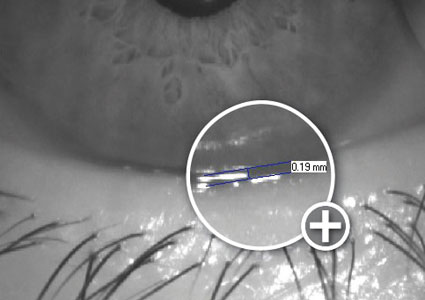

En Qvision, contamos con el equipo OCT, para poder medir cuantitativamente el espesor corneal y controlar sus posibles cambios secundarios al uso de lentes de contacto (edemas, moldeos…). También disponemos del Keratograph que nos mide el menisco lagrimal y sus posibles cambios inducidos por el uso de lentes.

Esta semana os presento un estudio realizado en el Contact Lens & Anterior eye, Assessment of corneal thickness and tear meniscus during contact-lens wear. En él se evalúan los efectos de siete lentes de contacto diferentes sobre el espesor corneal y sobre el volumen del menisco lagrimal, utilizando precisamente la OCT.

Se observó un pequeño adelgazamiento corneal posterior a las 12 horas de uso de las lentes. La lente Hilafilcon B causó el mayor aumento de espesor en la zona central, mientras que el Etafilcon A lo hizo en la córnea periférica media. Delefilcon A fue la lente que mostró un comportamiento más estable. También se encontró en general, un adelgazamiento del menisco lagrimal, el cual podría ser considerado como motivo de disconfort en el uso. La OCT ofrece la posibilidad de un seguimiento objetivo en el uso de lentes de contacto, aunque en este estudio no se encontraron cambios significativos producidos en el espesor central, sí se muestra la eficacia de esta medida cuantitativa con la OCT de polo anterior.